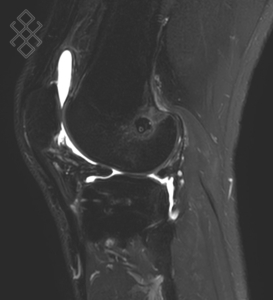

Arthro-IRM du Genou

La durée de l'examen est d'environ 20 minutes. Pour repérer la zone souahitée, le radiologue fera une scopie. Ensuite, il effectuera une désinfection puis une anesthésie locale. Pour l'injection du produit de contraste à base de gadolinium, il introduira une aiguille dans la zone repérée, puis il appliquera un pansement étanche. Enfin, vous serez installés afin d'effectuer l'IRM du genou.